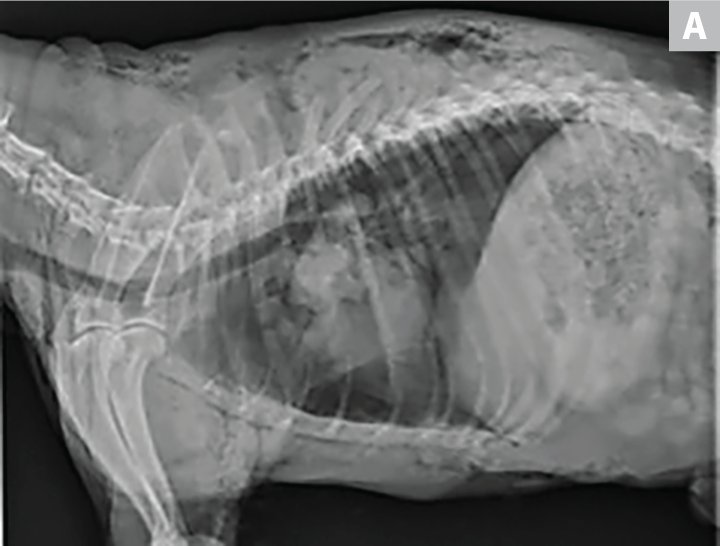

Bone feels pointy in chest area is this normal Golden Retriever Dog Forums shop, Skeletal abnormality in dogs and cats shop, Dog Anatomy Terminology JaneDogs shop, Canine Anatomy Veterian Key shop, Disabled Dog Improving Life for Your Dog shop, How to check your dog s body condition score tails shop, Measuring Proportions and Finding Landmarks Part 3 Showsight Magazine shop, Dog s Skeleton Emirates Dog Owners Society shop, Muscle of the Month Superficial Pectorals shop, Anatomy of a Boxer shop, Ribs vet Anatomy IMAIOS shop, Fitting a Harness shop, Dachshund Conformation Merrywind Teckels shop, Body The Dachshund Fit for function shop, Thoracic Wall Veterian Key shop, Breed Standard Forequarters 1 The Dachshund Breed Council UK shop, Chest Bone Deformity shop, Body The Dachshund Fit for function shop, Dog Canis lupus familiaris sternum 1021061 T30064 Osteology 3B Scientific shop, Showing how to bandage a dog s chest for fracture of ribs and other injuries to the chest as a result the dog often becomes unconscious soon after the accident. This may shop, Dog ribs hi res stock photography and images Alamy shop, Dog with Pectus carinatum. It was noted that a step is formed between. Download Scientific Diagram shop, The Body of the Dog The Chest Showsight Magazine shop, How to measure your dog for a shoulder or sidewalker harness Pawtrekker Articles shop, Form Follows Function Part 2 Canine Structure and Movement Showsight Magazine shop, Chest Bone Deformity in Dogs Symptoms Causes Diagnosis Treatment Recovery Management Cost shop, Any dogs here with pigeon chest Should I be worried r frogdogs shop, Pin page shop, Thorax Problems in Dogs Causes Signs Diagnosis shop, Thorax of the dog normal anatomy vet Anatomy shop, Prominent sternum Doberman Forum Doberman Breed Dog Forums shop, Flail Chest Diagnosis Bandaging Clinician s Brief shop, Chest Bone Deformities in Dogs Signs Causes and Care Guide Vet Answer Dogster shop, Guide How Should a Harness Fit on a Dog and More Tails of Connection How to connect with my dog online dog training strengthen your bond dog owners shop, Pin page shop.

Dog chest bone shop